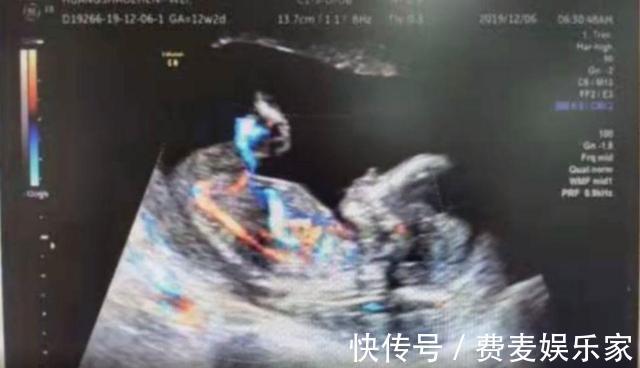

不久前,广西人民医院妇产科就住进了一位41岁的孕妇,这位孕妇姓黄。与一般孕妇不同的是,这位孕妇是宫外孕患者。宫外孕患者一般来说没有那么奇怪,但是奇怪的是,这位宫外孕患者在接受检查时,医生根本找不到怀孕的胎儿在哪儿。

因为小地方医疗条件有限,这位宫外孕患者辗转住到了广西人民医院。广西人民医院妇产科主任医师在接受采访人员采访时说道,最开始查出来只是早孕,查不出胚胎在哪里,过了15周之后,在她的子宫内还是找不到胚胎。

后来经过一系列专业检查,医生最终确定胎儿在腹腔内存活的,已有4个月。如果遇到这种情况,不及时进行手术。不仅对母体造成伤害,甚至会有生命危险。为了保住胎儿和大人。医院的妇产科团队立即根据实际情况迅速的制定出相应的实施方案,并及时根据方案进行了手术。手术过后,由于病人身体比较虚弱,目前还在进一步的康复治疗中。